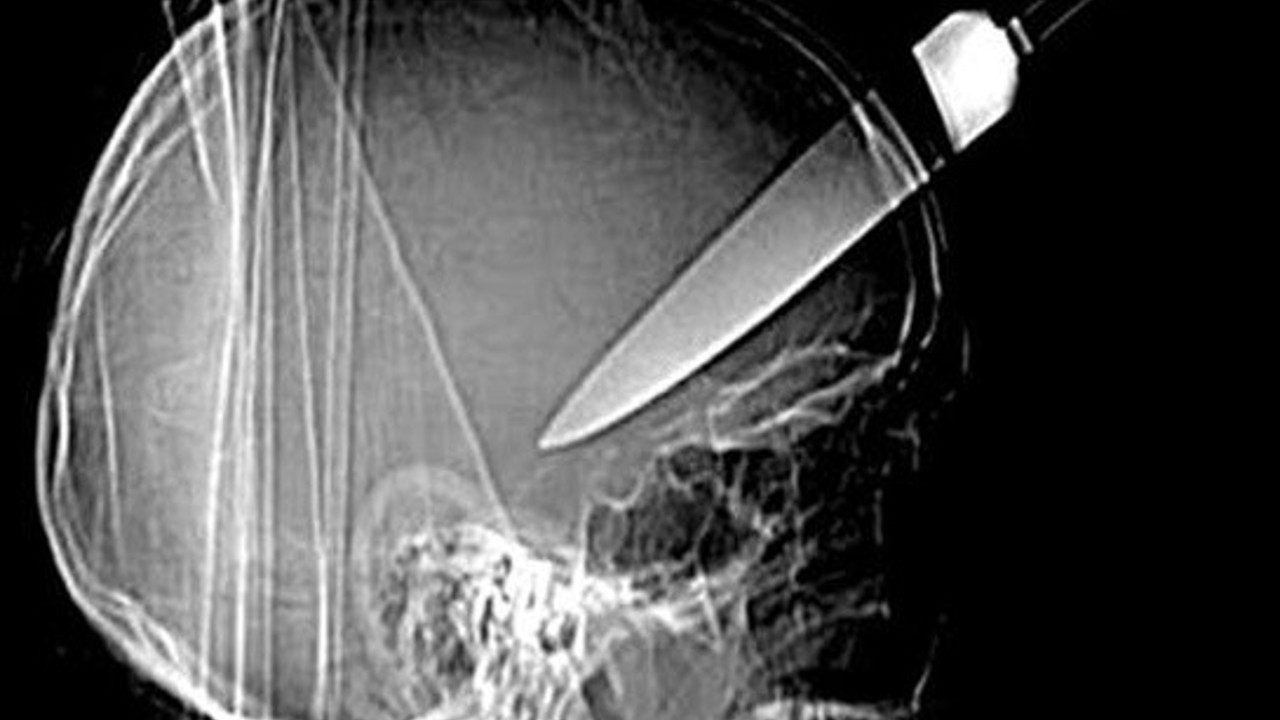

Bu röntgen filmleri görenleri şoke ediyor

Şoke eden röntgen filmleri Galerinin tamamı için tıklayınız Bu röntgen filmleri görenleri şoke ediyor